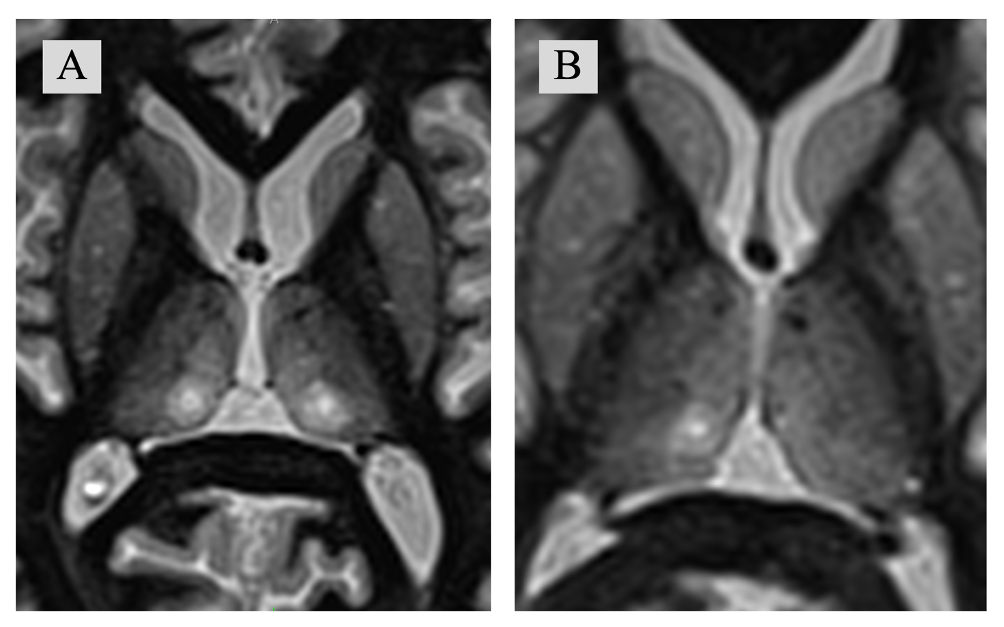

Согласно отчету FUS Foundation – менее 1% лечений с использованием транскраниального ФУЗ проводятся у пациентов с болевыми синдромами19. В опубликованных работах основной мишенью для лечения болевых синдромов методом ФУЗ являются CL и VPL ядра таламуса20. Однако с учетом возможности проведения как деструкции, так и нейромодуляции фокусированным ультразвуком, возможно расширение списка «таргетов» для проведения вмешательств. В Российской федерации ФУЗ внедрен с 2020г, в основном применяется для лечения экстрапирамидных заболеваний (Эссенциальный тремор, болезнь Паркинсона). В условиях «ФГБНУ Российского Центра Неврологии и Нейронаук» проведены несколько хирургических вмешательств транскраниальным МР-направленным фокусированным ультразвуком для лечения хронических болевых синдромов. В качестве «мишени» использовались CL ядра таламуса - как билатерально, так и унилатерально (рис. 1). Следует отметить, что вероятность изолированного воздействия на CL низкая, и при проведении стереотаксических вмешательств по поводу болевых синдромов (как радиочастотным методом, так и с использованием лучевой терапии и ФУЗ), воздействие охватывает и другие структуры, расположенные в непосредственной близости от CL. С учетом короткого катамнеза, результаты лечения пациентов не отражены в данной работе.

Рисунок 1: На послеоперационных снимках в аксиальной плоскости на уровне соответствующему D7 по стереотаксическому атласу Morel et. Al представлены А – Очаги воздействия после билатеральной CLT; B – Очаг деструкции после правосторонней CLT. (CLT: Центрально-латеральная таламотомия).